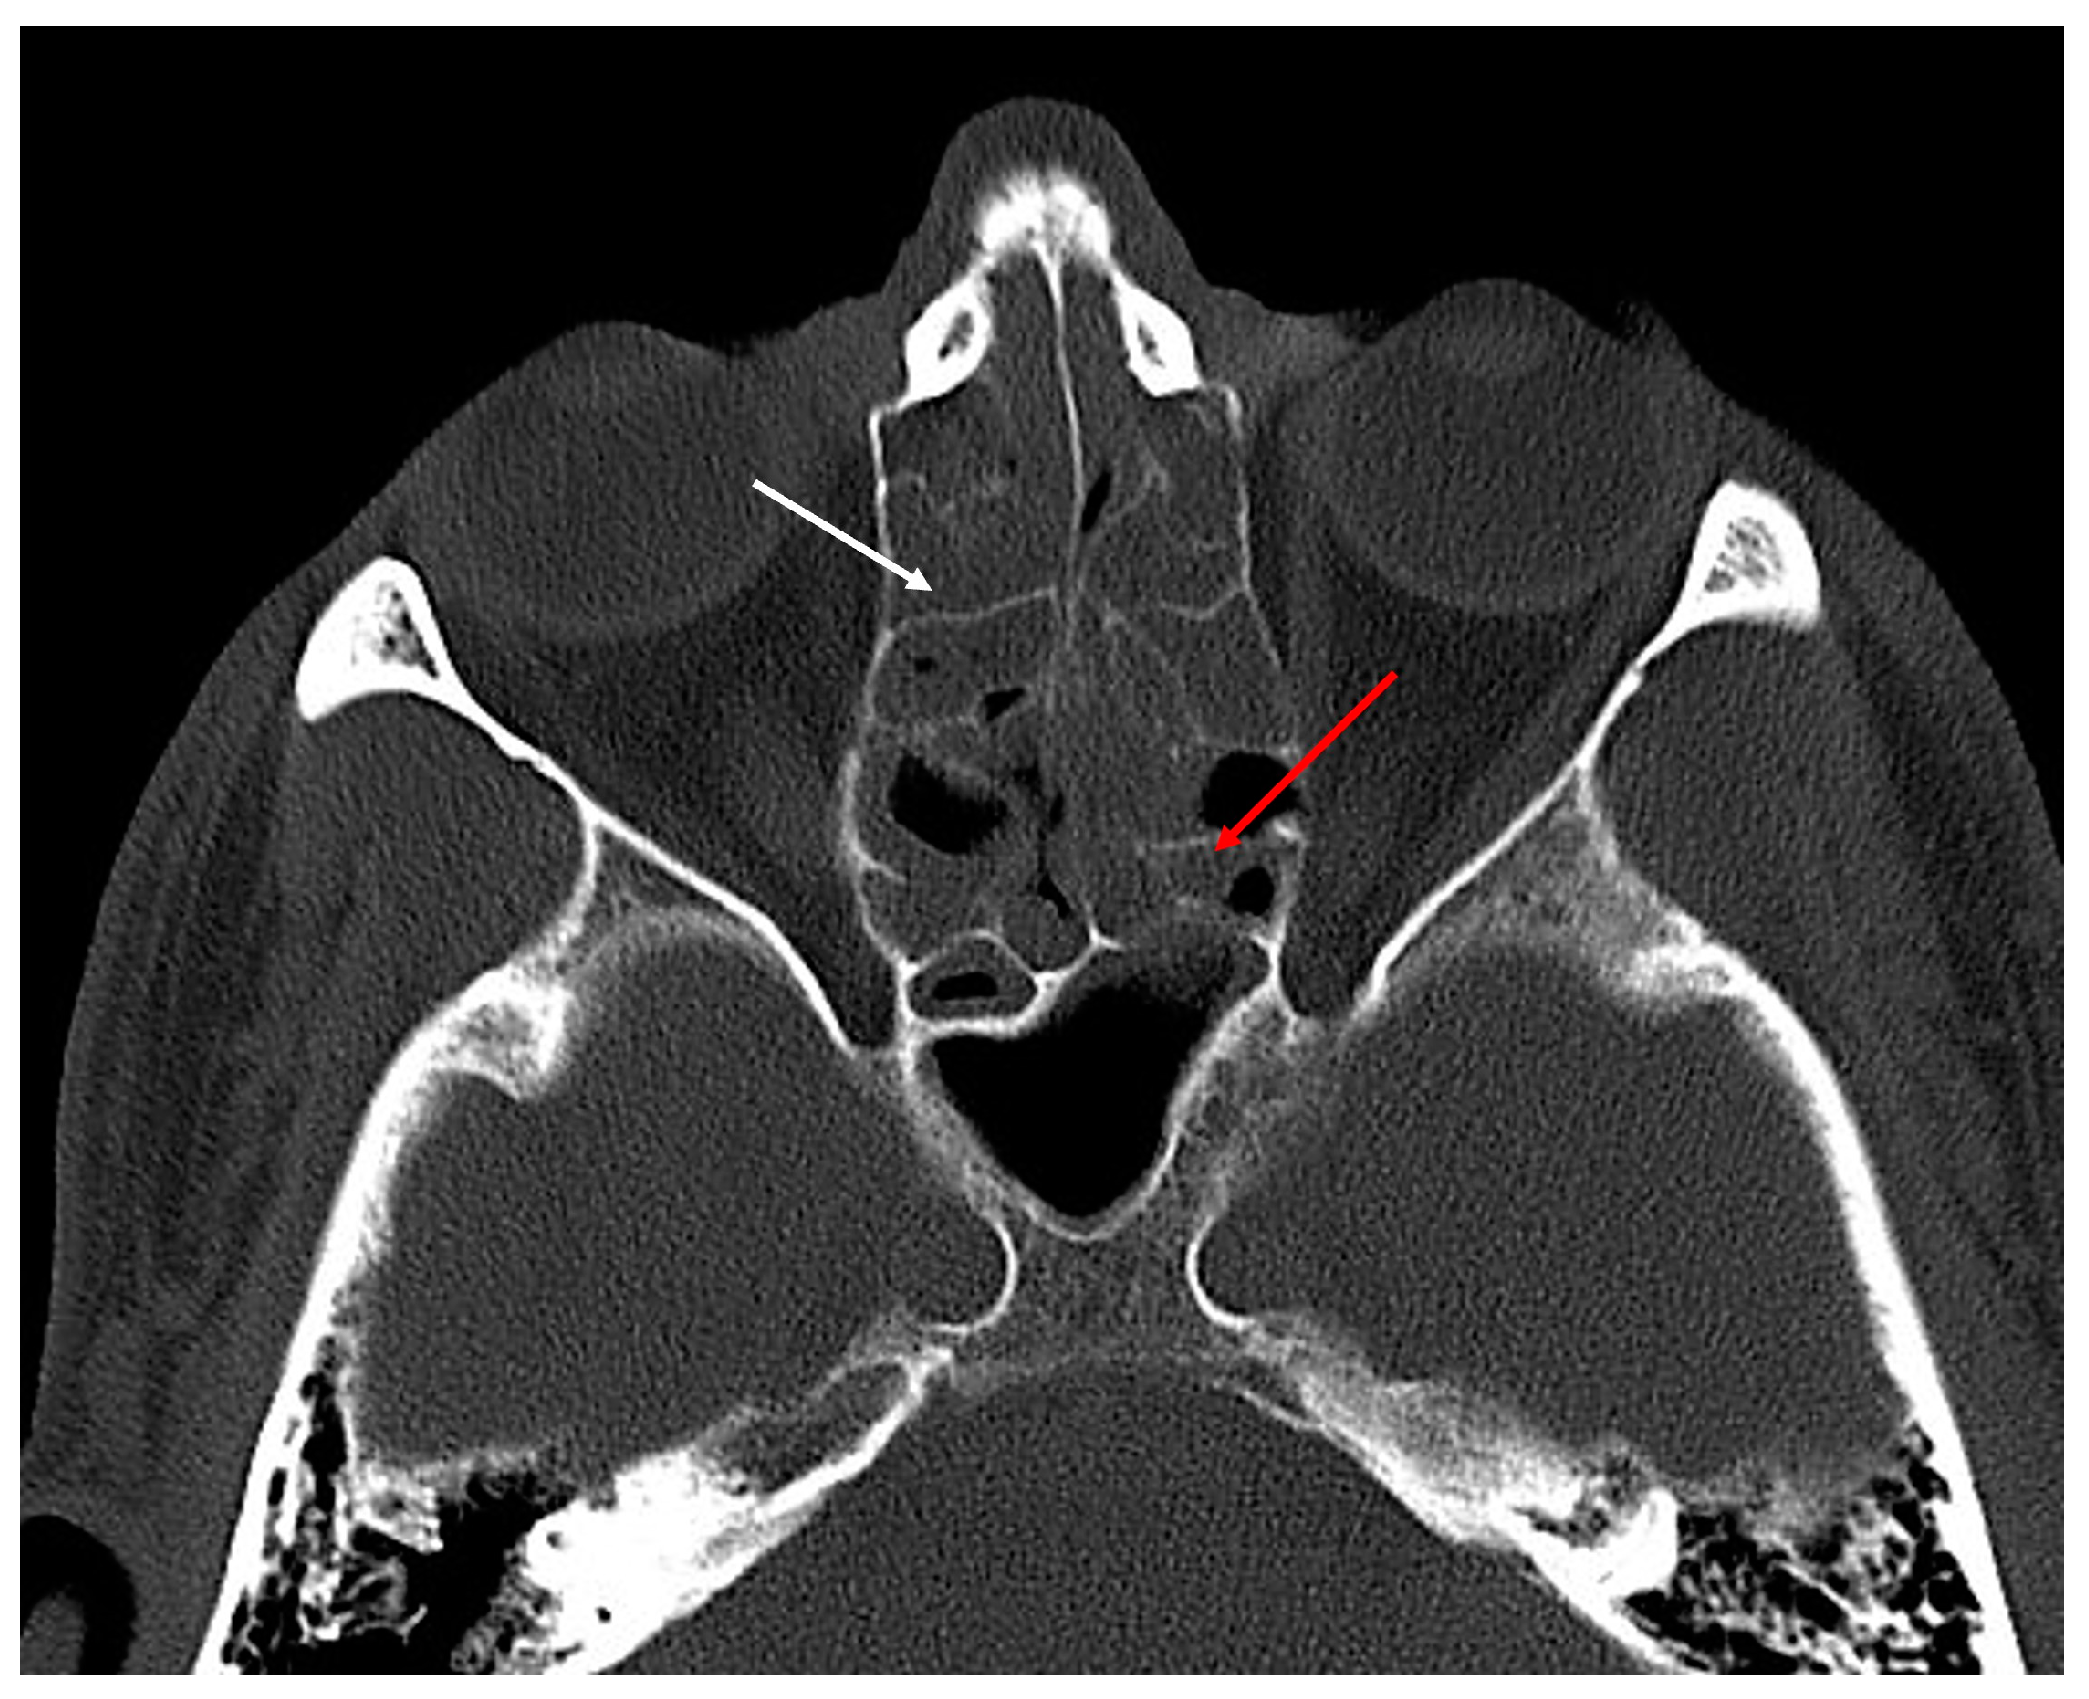

- Residual bony septae in anterior ethmoids, which were defined as >3 bony septae measuring 3 mm along lamina papyracea/skull base/middle turbinate on preoperative sinus CT (Figure 3) [residual agger nasi cells were excluded from this category and considered as residual frontoethmoidal cells];

- Residual bony septae in posterior ethmoids, which were defined as >3 bony septae measuring 3 mm along lamina papyracea/skull base/middle turbinate on preoperative sinus CT (Figure 3);

| Residual bony septae in anterior ethmoids | 43 (62.3%) | 40 (93.02%) |

| Residual bony septae in posterior ethmoids | 46 (66.67%) | 43 (93.47%) |